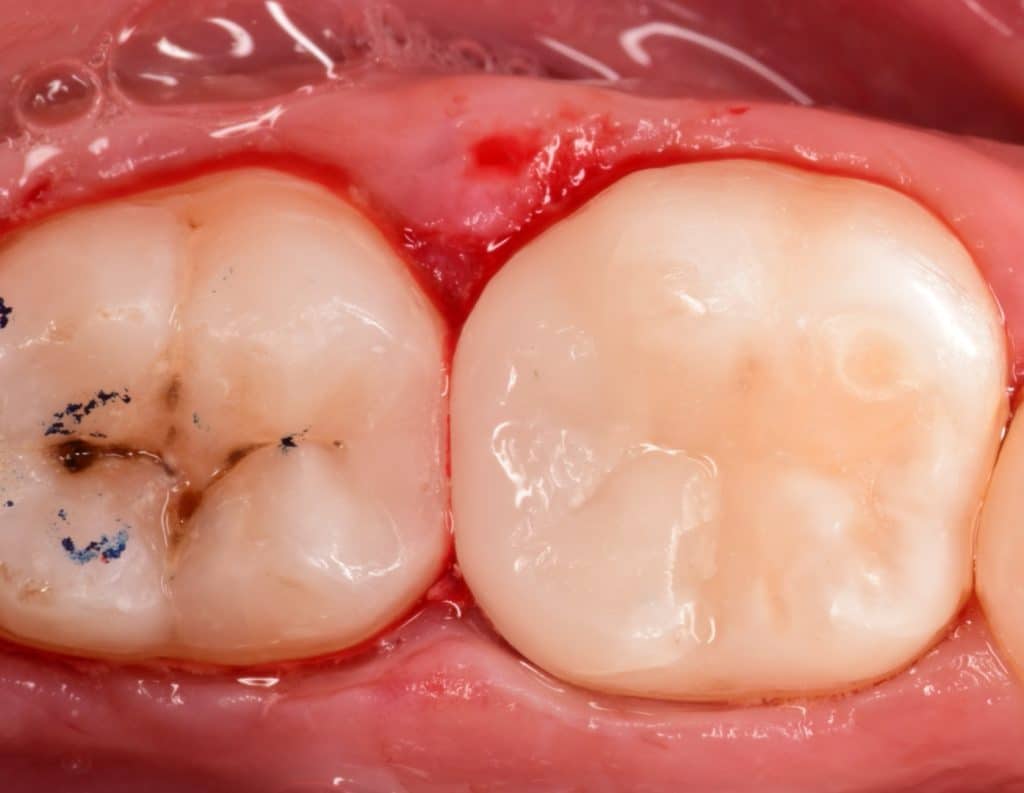

Direct posterior composite before and after 2 weeks later .

Initial situation showing badly restored lower first molar with amalgam filling

2 weeks later look to the healthy gingival tissue